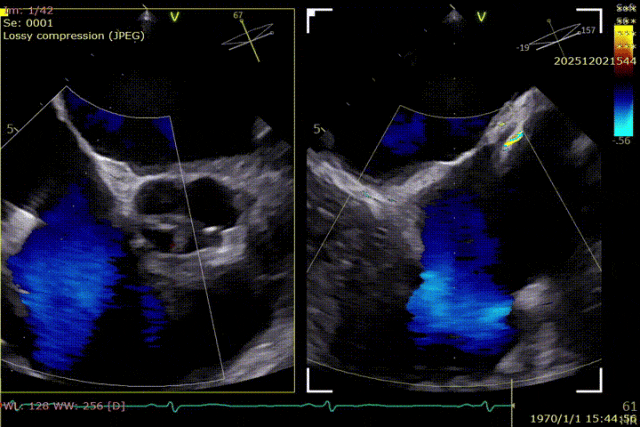

During the procedure, close collaboration was maintained with Dr. Yang Yan (anesthesiologist, Department of Anesthesiology) and Dr. Niu Ming (echocardiography specialist, team of Director Zhai Hong, Department of Cardiac Ultrasound). Guided by transesophageal echocardiography and assisted by DSA imaging, the tricuspid annular structure and regurgitation jet direction were precisely assessed. Ultimately, two 12T K-Clip® devices were successfully implanted. Immediate postoperative echocardiographic evaluation showed a significant reduction in tricuspid regurgitation from 4+ preoperatively to 1+, with a marked decrease in annular area. The surgical outcome was satisfactory.

Echocardiographic: Severe tricuspid regurgitation (grade 4+), with the regurgitant jet mainly located at the posteroseptal and central regions. No significant dilatation of the tricuspid annulus is observed. Mild myxomatous degeneration of the tricuspid leaflets is present, showing Barlow-like morphology, with leaflet prolapse of 3.7 mm in height.

Surgical Outcome

Preoperative Regurgitation: 4+

Annulus Area: 11.3 cm²

Postoperative Regurgitation: 1+

Annulus Area: 4.9 cm²